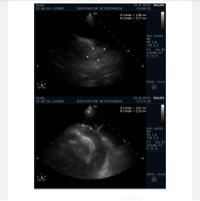

Fizemos uma série de exames com cardiologistas e descobrimos a existência de um tumor no coração do Noah, tumor este que, até agora, ainda não conseguimos descobrir se é malígno ou benigno. Este tumor, quando inflamado, acaba gerando e acumulando líquido no pericárdio, ao redor do coração do Noah, e isso faz com que o coraçãozinho dele fique apertado, funcionando com dificuldade. O coração, por estar em sofrimento, acaba não conseguindo bombear sangue o suficiente para o restante do corpo, fazendo com que os órgãos fiquem sobrecarregados e que mais líquido se acumule, se espalhando também para a região abdominal. Mesmo já tendo feito cerca de quatro drenagens (sendo três no coração e uma no pulmão, que também já acumulou líquido), este problema fica indo e vindo, nos deixando desamparadas. Ele, quando está com líquido retido, não consegue deitar direito para dormir, fica dormindo sentado, perde o apetite, fica com a respiração pesada…

Já fizemos rifas e contamos com doações nas redes sociais, mas as nossas idas ao veterinário tem sido semanais, às vezes mais de duas vezes por semana, e o dinheiro tem sido uma grande questão. Agora, o próximo passo é fazer uma tomografia para descobrirmos sobre o tumor que, sendo benigno, o Noah poderá passar por uma cirurgia para a retirada do pericárdio, que vai impedir que esse líquido volte a se acumular, podendo dar a ele uma vida normal.